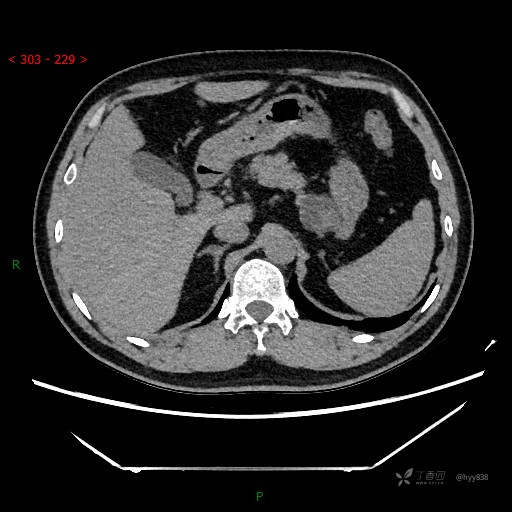

增强动脉期